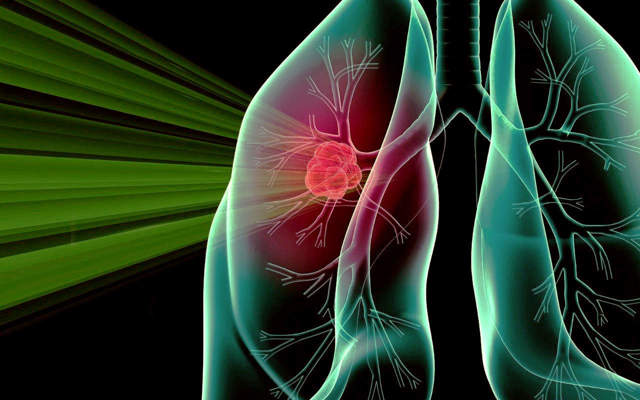

Позитронно-эмиссионная томография (ПЭТ)

Диагностика с помощью ПЭТ основывается на действии радиоактивных элементов с коротким периодом полураспада, создающих изображение органа.

Если КТ и МРТ дают представление об анатомическом строении органа, ПЭТ оценивает процессы метаболизма и функционирование тканей.

Методика позволяет оценить интенсивность развития и идентифицировать вид раковых клеток внутри конкретного новообразования.

Человек во время процедуры облучается аналогично 2 рентгеновским снимкам, поэтому используется препарат, содержащий радиоактивные элементы с коротким периодом полураспада. Вещество концентрируется, и начинает выделять позитроны. Когда позитроны сталкиваются с электронами, происходит реакция с образованием гамма-излучения.

Аппарат ловит эти излучения, фиксирует локацию, где накапливается препарат. Найти опухоль можно и за счет реакции препарата с глюкозой. Углеводы — главный источник энергии в организме, поэтому растущая опухоль активно их использует.

Если в организме есть место, где большая концентрация глюкозы, можно предположить, что это злокачественное новообразование.

ПЭТ можно использовать в комплексе с КТ, в методике диагностики под общим названием ПЭТ-КТ. Такой способ намного эффективнее в определении стадии развития патологии.

Позитронно-эмиссионная томография

Один из самых современных методов, основанный на способности клеток злокачественной опухоли избирательно поглощать определённые вещества.

Перед исследованием в организм пациента вводятся фармпрепараты с коротким периодом полураспада, которые накапливаются исключительно в тканях злокачественной опухоли.

Следующим этапом выполняются снимки в различных проекциях, на которых можно четко локализовать распространение раковых клеток, выявить очаги метастазов, недоступные при других вариантах диагностики.

Подобная диагностическая методика позволяет получить оценку работоспособностей тканей и активности обменных процессов. Изображения пострадавшего участка выполняются за счет влияния радиоактивных веществ с кратким периодом воздействия. Позитронно-эмиссионная томография позволяет выполнить изображения внутриорганных структур в 3D формате.

ПЭТ.

Пациенту вводят радиоактивный препарат с кратковременным действием, а после этого проводят сканирование. В процессе обследования, пациент получает облучение, которое по степени сопоставимо с флюорографией.